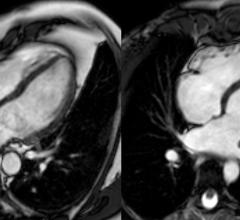

Cardiovascular Clinical Studies

This channel includes news and new technology innovations from cardiovascular clinical trials. These clinical studies include all cardiac subspecialties.